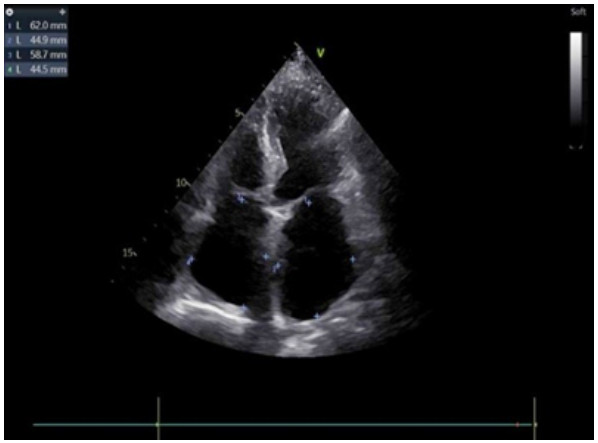

腹主动脉CTA成像示:腹主动脉近末端处-双侧髂总动脉-双髂外动脉、右髂内动脉、左髂内动脉起始部未见对比剂充盈,考虑腹主动脉急性闭塞(见图 4)。

| 注:A为冠状位,B为矢状位;腹主动脉远端未见对比剂充盈(箭头处) 图 4 患者主动脉CTA血管成像 |